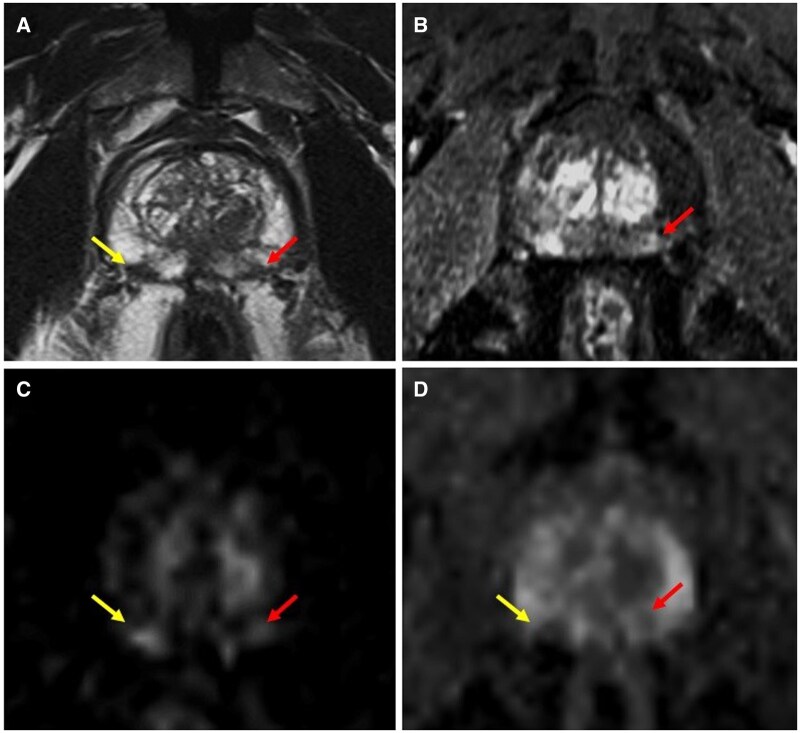

Objectives: The study aims to evaluate Prostate Imaging-Reporting and Data System 4 (PI-RADS 4) lesions, including those with primary diffusion restriction (diffusion-weighted imaging score 4) and those upgraded from PI-RADS 3 due to positive dynamic contrast-enhanced findings, and to compare outcomes between these groups while also assessing cancer detection rates and prostatitis between upgraded cases and PI-RADS 3 lesions.

Methods: In this single-center cohort study, peripheral zone lesions classified as PI-RADS 3 and 4 by multiparametric MRI and biopsied via MRI/transrectal ultrasound-guided targeted biopsy were analyzed.

Results: Of 420 peripheral zone lesions from 272 patients, 202 were PI-RADS 3, 81 PI-RADS 3 + 1, and 137 PI-RADS 4. Cancer detection rates significantly differed between PI-RADS 3 + 1 and PI-RADS 4 (38.3% vs 73% for overall cancer; 6.2% vs 30.7% for clinically significant cancer, P < .001). PI-RADS 3 + 1 lesions had significantly higher cancer detection rates than PI-RADS 3 lesions (38.3% vs 19.8%, P  = .001). Prostatitis was significantly more prevalent in PI-RADS 3 (34.7%) and PI-RADS 3 + 1 (29.6%) than in PI-RADS 4 (10.9%) lesions (P < .001).